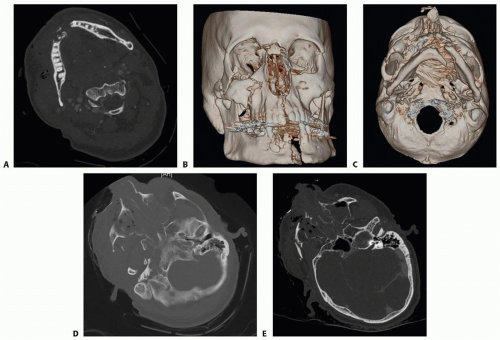

Axial, coronal, and sagittal cuts are utilized to visualize specific fracture patterns and reformatted to generate three-dimensional (3D) images (FIG 1A-C).

A standard head CT is better used as a screening tool, given its limited ability to visualize the zygomatic arch as well as the complete maxilla and mandible (FIG 1D,E).

A more complete craniomaxillofacial CT should extend from the vertex of the skull to the symphysis of the mandible.

3D CT imaging affords additional understanding of the spatial relationship of fracture fragments but does not provide information about soft tissue deformities.